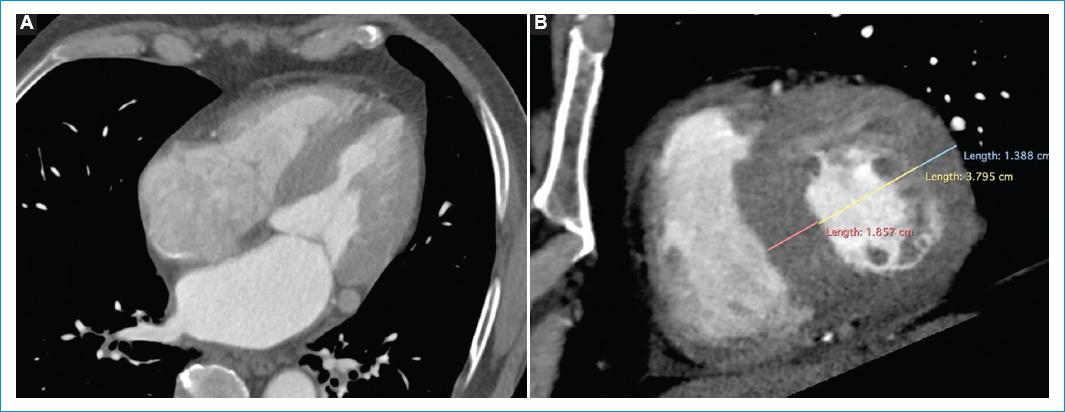

Cinco meses después consultó por cuadro de una semana de palpitaciones, disnea de pequeños esfuerzos y edema en miembros inferiores. El ECG nuevamente en ritmo de FA. Se realizó nuevo ecocardiograma transtorácico en el que se evidenció hipocinesia global grave y FEVI del 25%. Se ordenó angiotomografía cardíaca para valorar la integridad de las venas pulmonares con el objetivo de llevar a un segundo procedimiento de aislamiento eléctrico de venas pulmonares; sin embargo, esta última refirió hipertrofia de la pared septal de 17 mm y posible amiloidosis vs. miocardiopatía hipertrófica (Fig. 1). Ante el hallazgo tomográfico fue llevado a resonancia magnética (RM) cardiaca contrastada en la cual se documentó disfunción sistólica biventricular (FEVI 35% y TAPSE 8 mm), dilatación biauricular, alteración de la cinética entre el pool sanguíneo y el miocardio, realce subendocárdico difuso con distribución no coronaria con extensión al ventrículo derecho y ambas aurículas, y aumento grave del volumen extracelular (51%), hallazgos que fueron compatibles con amiloidosis cardiaca (Fig. 2).

Figura 1 Angiotomografía de arterias coronarias en 75% del intervalo R-R con reconstrucción multiplanar en cuatro cámaras (A) y eje corto (B) demuestra dilatación biauricular e hipertrofia grave del septum interventricular y de la pared lateral del ventrículo izquierdo.